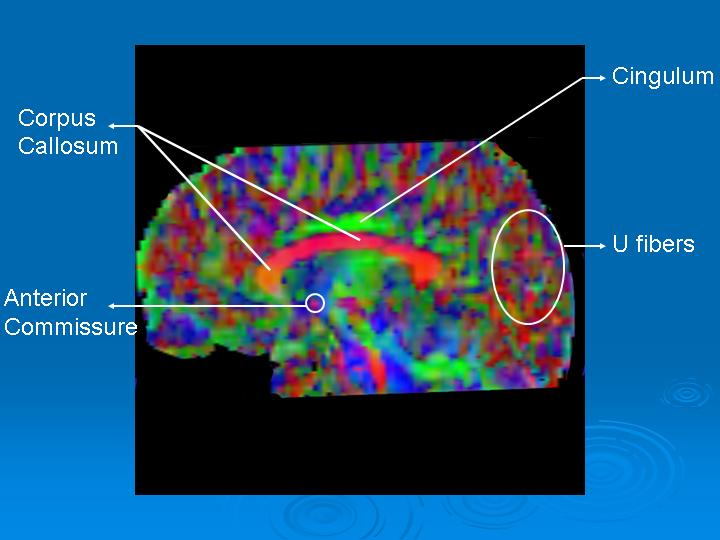

The sagittal plane (figure 3) best provides information on interhemispherical fibers going right to left or viceversa (red) or anterior-posterior (green). These are the corpus callosum and the anterior commissure.

Subcortical U fibers appear various colors due to multiple intersecting planes.